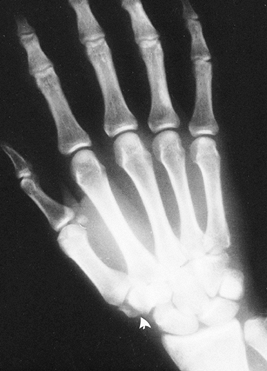

Make a 3.0- to 4.0-cm longitudinal incision along the radial border of the flexor carpi radialis (FCR) tendon (Fig. 42.10). Curving the distal portion of the incision into the wrist flexion crease facilitates exposure.

Figure 42.10. A: Radiograph of a nonunion of the scaphoid. B: At 3 months postoperatively, the fracture had healed and there was radiographic evidence of bone revascularization. C: A deep trough across the fracture site (arrows). D: Trough filled with an autogenous corticocancellous iliac bone graft. E: Radiograph taken 4 months after surgery shows complete consolidation of the graft. -